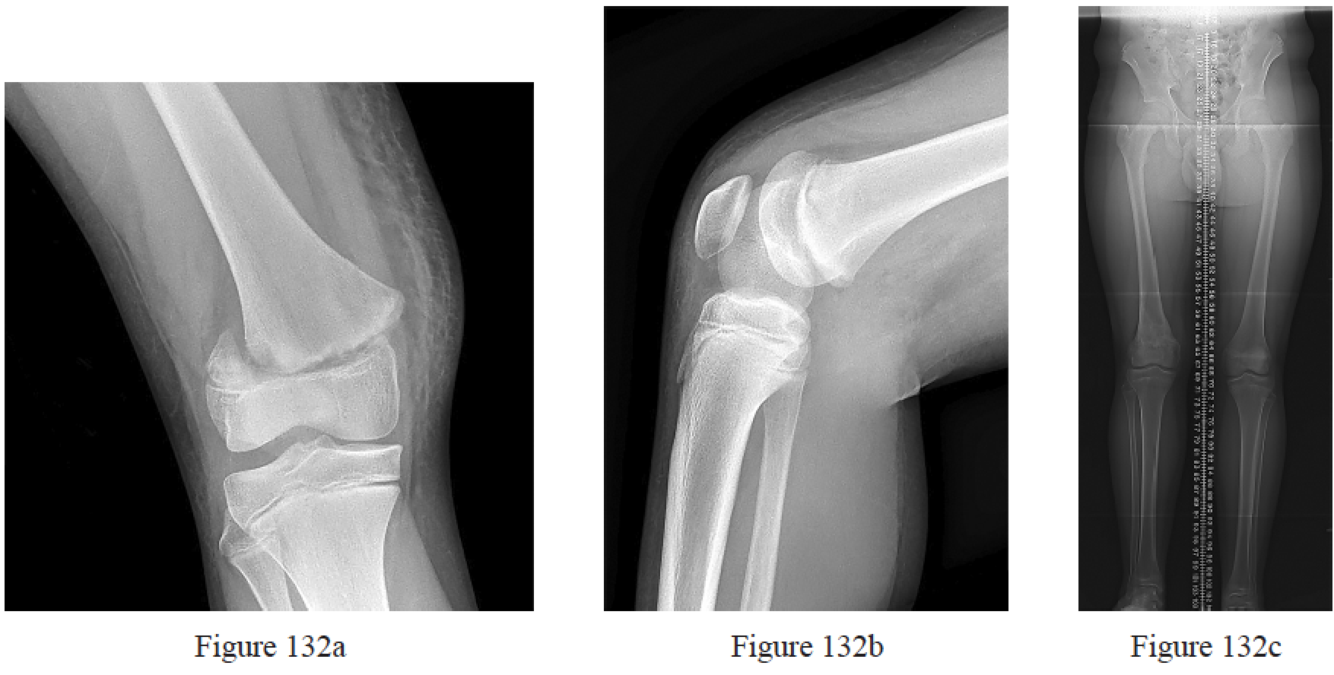

Ringus VM, Lemley FR, Hubbard DF, Wearden S, Jones DL. Lateral tibial plateau fracture depression as a predictor of lateral meniscus pathology. Orthopedics. 2010 Feb;33(2):80-4. doi: 10.3928/01477447- 20100104-05. PubMed PMID: 20192139.

Stahl D, Serrano-Riera R, Collin K, Griffing R, Defenbaugh B, Sagi HC. Operatively Treated Meniscal Tears Associated With Tibial Plateau Fractures: A Report on 661 Patients. J Orthop Trauma. 2015 Jul;29(7):322-4. doi: 10.1097/BOT.0000000000000290. PubMed PMID: 25635356.